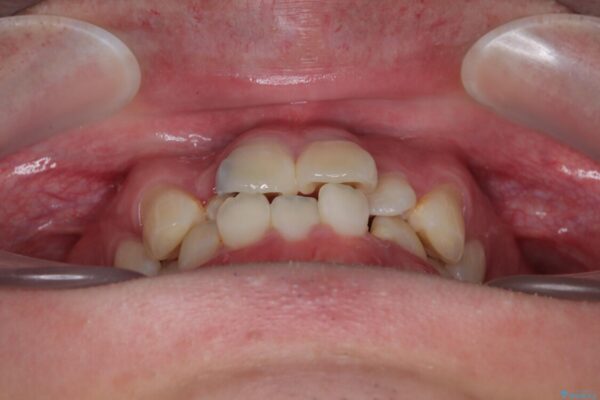

「歯並びがデコボコしていて、上下の中心がズレているのが気になる…」という悩みで来院された患者さまの症例をご紹介します。

・上下ともに歯がきれいに並びきらず、がたつきが見られました。

・上下の前歯の中心(正中)がずれています。

・特に上顎の幅が狭いため、下顎の歯列も内側に入り込み、歯が並ぶスペースが不足していました。

• 1年でここまで変わる!歯列のがたつきと正中のズレを改善した矯正治療(メタルブラケット×MARPE) 治療前画像